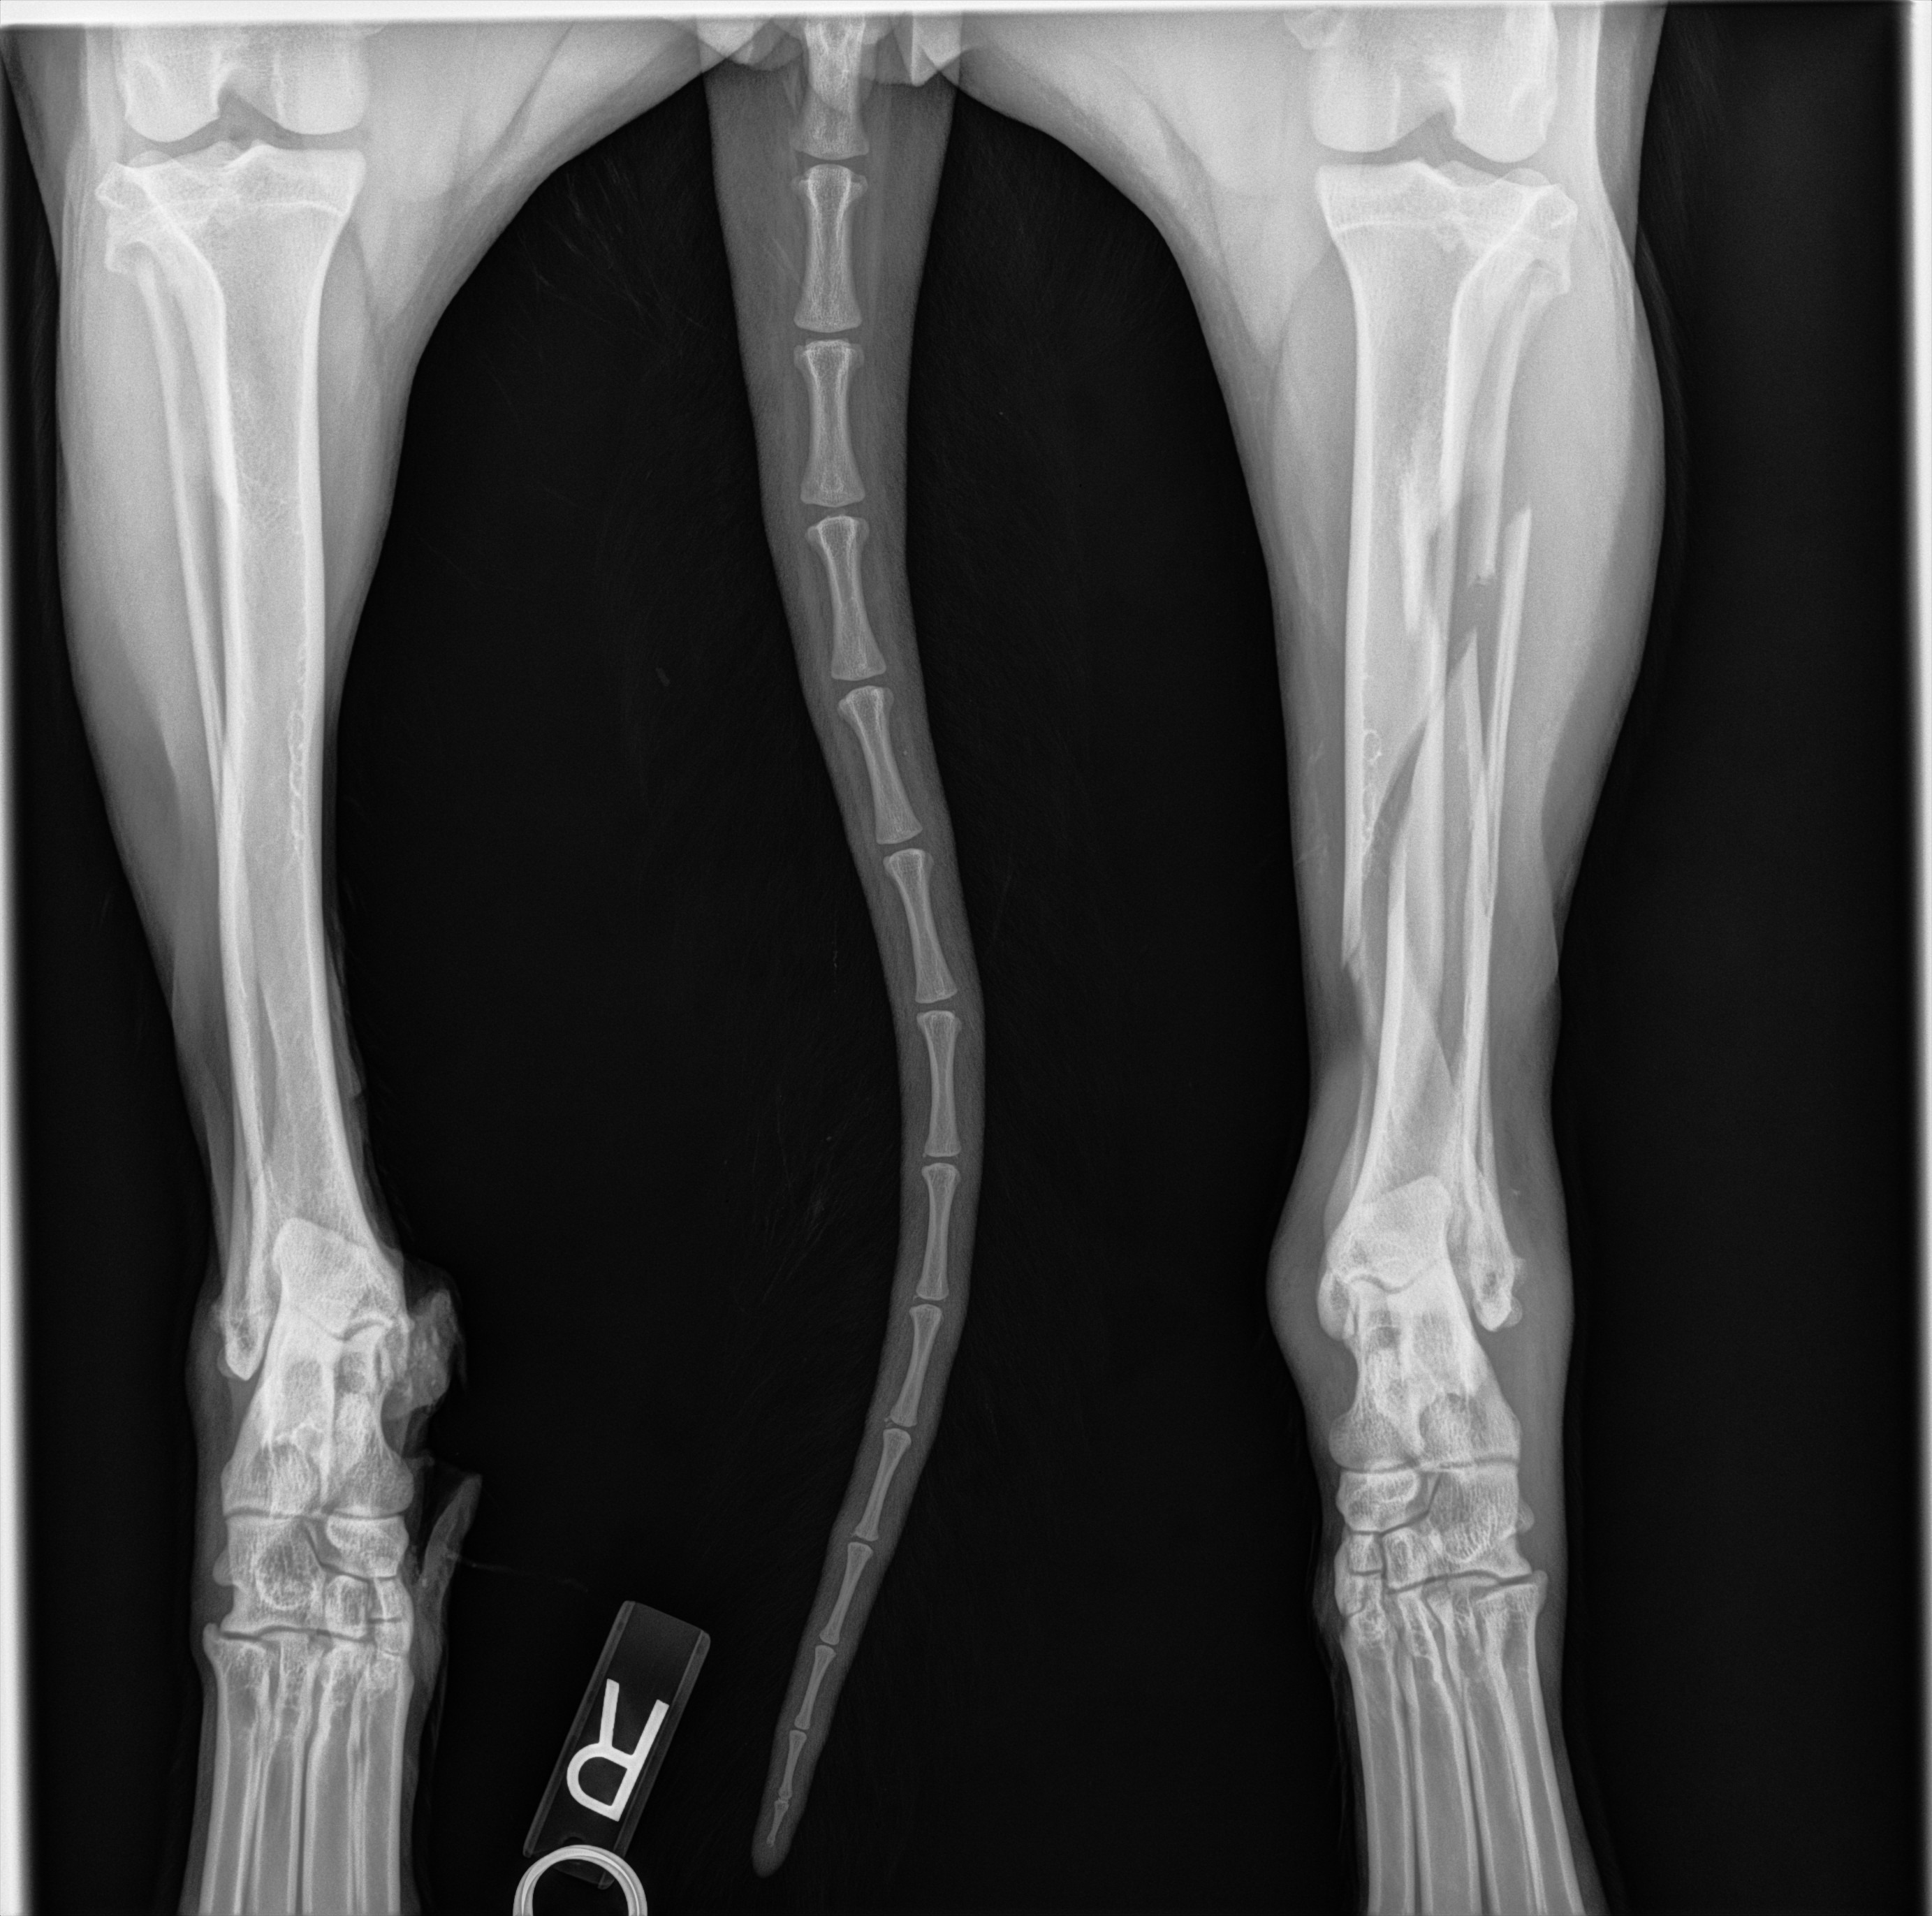

We heard the impact and found her badly injured. She was rushed to the emergency vet, where X-rays showed multiple fractures in her back leg.

The doctors gave us three options: euthanasia, amputation, or a complex orthopedic surgery to try to save her leg.